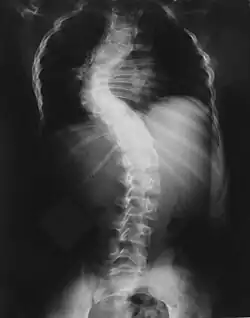

Проявления нейрофиброматоза I типа часто начинаются со сколиоза (искривления позвоночника), затем возникают трудности в обучении, проблемы со зрением и эпилепсия.

Костные изменения

Для выраженного нейрофиброматоза характерна деформация позвоночника в виде сколиоза, возможны краевые дефекты тел позвонков, их суставных и поперечных отростков, расширение межпозвоночных отверстий и эрозии их краёв, узуры нижних краёв задних отделов рёбер, вызванные давлением нейрофиброматозных узлов[36].

Длинные трубчатые кости могут быть атрофичными, изогнутыми, иногда же, наоборот, гипертрофированными, утолщёнными. Компактное вещество в гипертрофированной кости утолщено. На поверхности кости видны периостальные гребни, иногда обнаруживаются и параостальные окостенения. Внутрикостные нейрофибромы в трубчатых костях выглядят как ограниченные вздутия и кистовидные образования[36].

При вовлечении в процесс костей черепа обнаруживается его асимметрия. Особенно выраженной она бывает при деформациях его лицевой части и стенок глазницы. В костях свода черепа возможны дефекты и узуры, участки атрофии кости или явления гиперостоза[36].